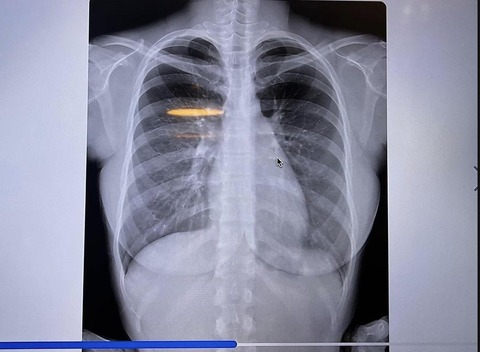

タレント、女優の鈴木ふみ奈(32)が14日、胸部レントゲン写真をツイッターに投稿した。

人間ドックを受診した際のもので、「私の胸部レントゲン!笑」の文言とともに正面・左右から撮影したものなど4枚を掲載。「これで私の胸が天然な事は証明できたのかな?」と〝加工なし〟を強調した。